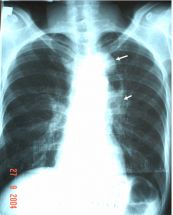

Lao hang phổi phải có mức nước mức hơi trên phim chụp x quang ngực. Để hiểu rõ hơn về bệnh lý này mời các bạn cùng tham khảo bài viết ngay dưới đây nhé!